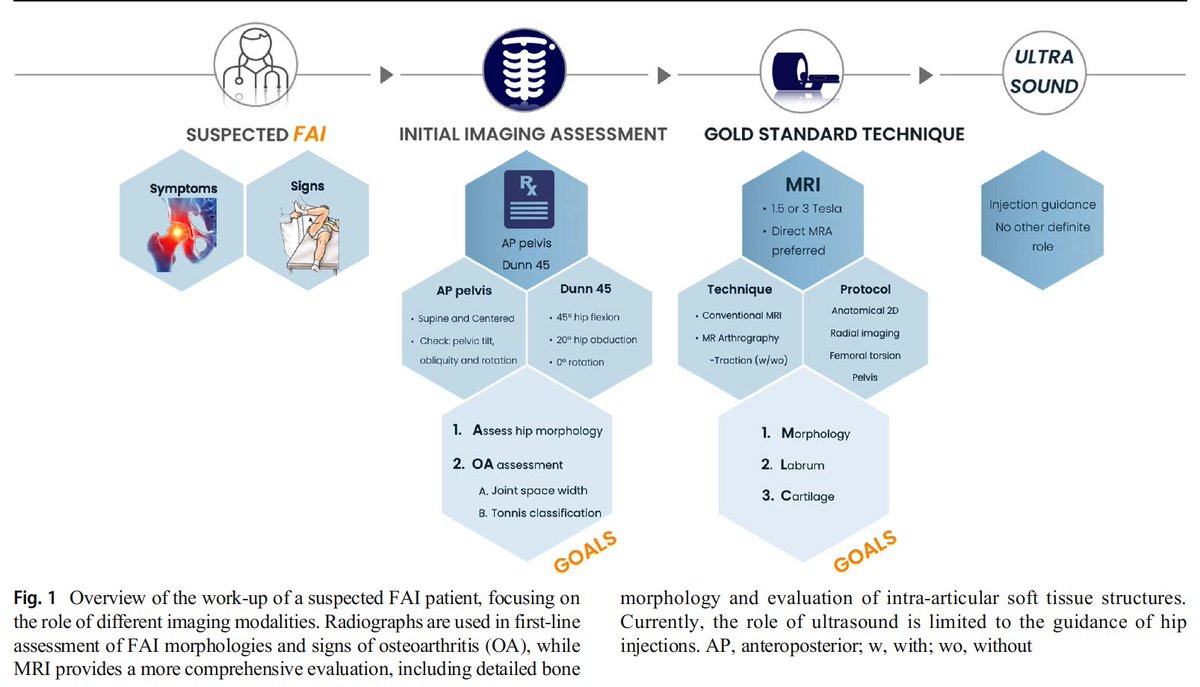

FAI week! Parts 2 & 3 of Lisbon "trilogy" on FAI imaging Control Hip Hype!

Part 1: https://pubmed.ncbi.nlm.nih.gov/32405754/

Part 2: https://pubmed.ncbi.nlm.nih.gov/33411052/

Part 3: https://pubmed.ncbi.nlm.nih.gov/33411053/